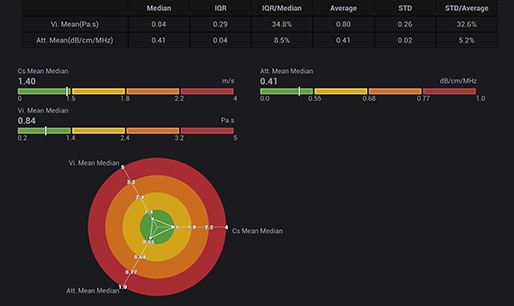

STVi enables the quantitative evaluation of tissue viscosity and

provides real-time multi-parameter imaging, offering a more

comprehensive approach to imaging diagnosis and quantitative

analysis of chronic liver diseases, breast lesions, and other

conditions.

Dual quantitative coefficients

Chronic liver disease assessment

Multiple quantification tools

Breast tumor assessment